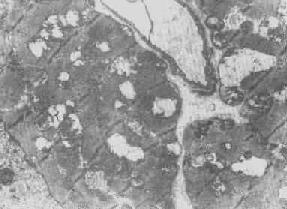

2.次级溶酶体为除溶酶体的水解酶外尚含有其他外源性或内源性物质并已参与细胞内消化过程的溶酶体(图1-14),亦即含有溶酶体酶的各种噬体,因而称为吞噬溶酶体(phagolysosome),乃由吞噬体与初级或次级溶酶体融合而成。

图1-14 肝细胞内次级溶酶体

贮存在溶酶体中的物质被溶酶体酶加以降解(消化)。但有时进入细胞的物质为量过多,超过了溶酶体的处理能力,于是乃在细胞内贮积,例如各种原因引起的蛋白尿时可在肾近曲小管上皮细胞中见到玻璃滴状蛋白质的贮积(所谓玻璃样小滴变性)。在电镜下可见这种玻璃样小滴乃载有蛋白质的增大的溶酶体,故实质上这往往是细胞功能增强的表现,与真正的变性有所不同。